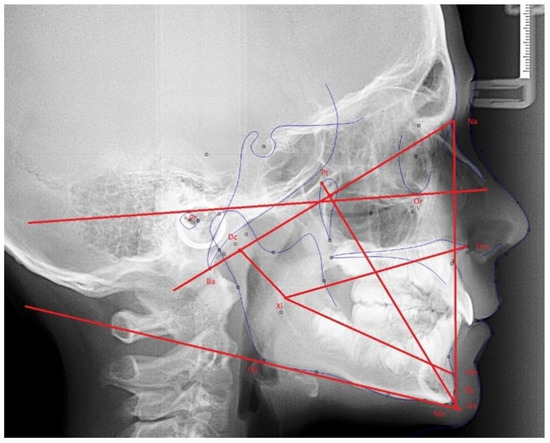

2.3. Data Collection for Ricketts’ VERT Index and Related Measures